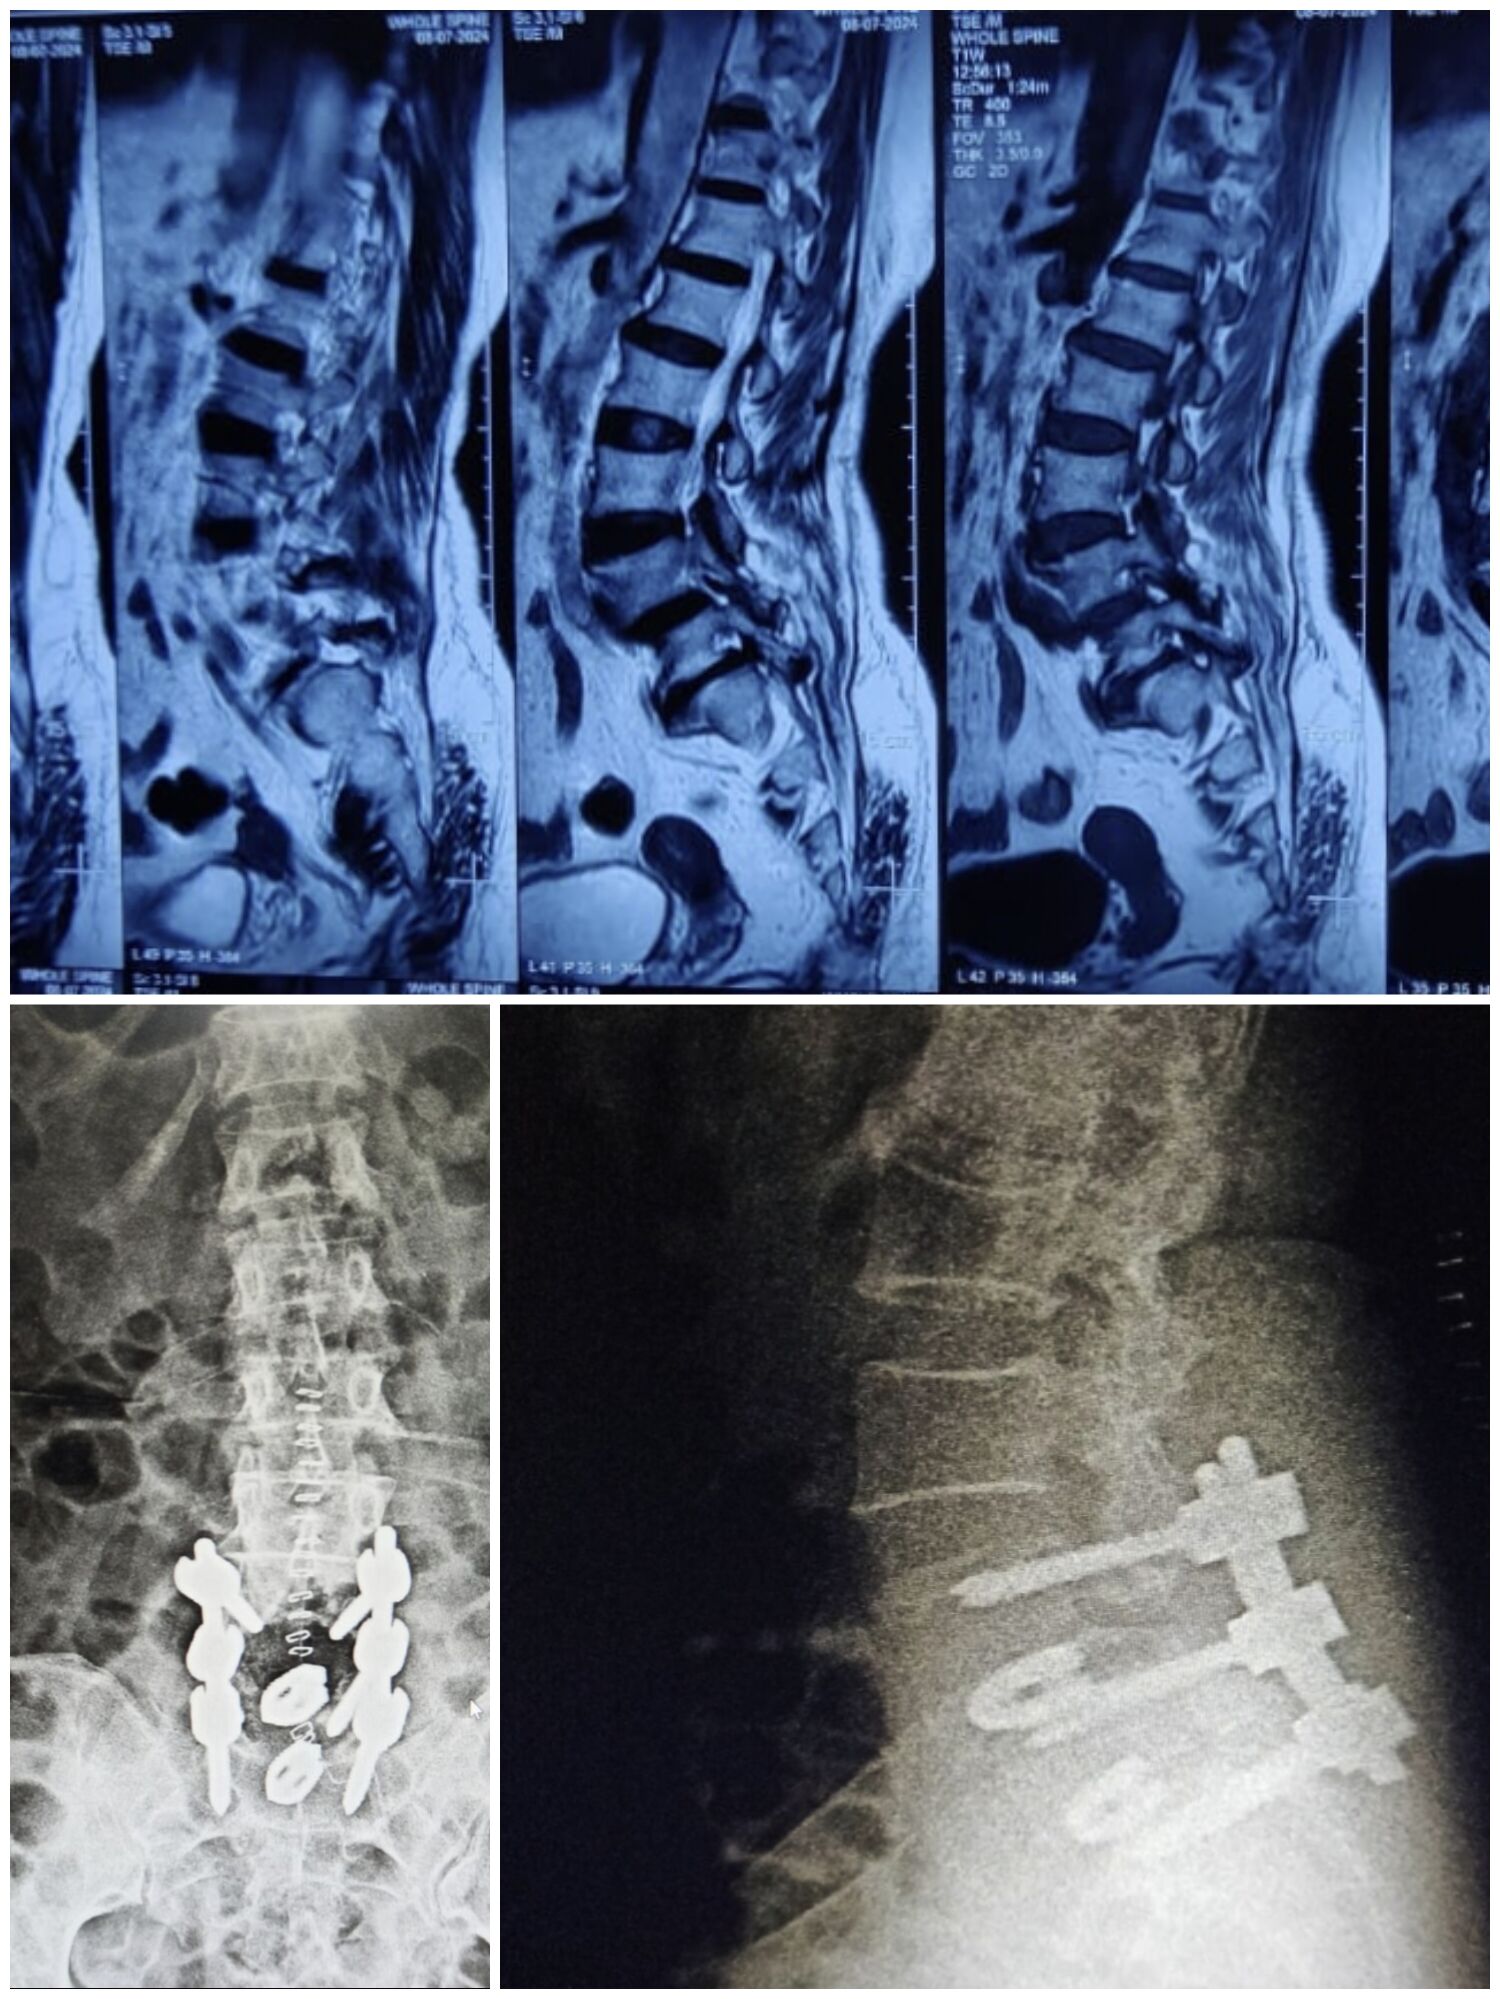

The damaged or slipped disc is removed.

A cage (spacer) filled with bone graft is placed between the vertebrae.

Screws and rods are fixed to support the spine.

Over time, the bone graft fuses the two bones, giving permanent stability.